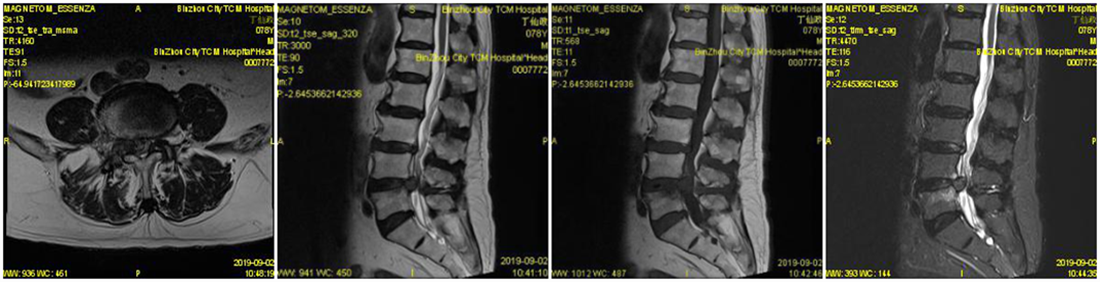

入院后经过详尽询问病史、仔细查体及全面影像检查及分析。患者存在腰部脊椎的纵向的失稳,在站立时存在椎间隙变窄,椎间盘组织进一步突出明显。针对此病患的传统理念,是行腰椎椎弓根螺钉固定加以椎间隙植骨融合术治疗,但由于该患者年龄较大,若以传统理念进行手术,对此高龄患者的创伤较大,恢复期较长。综合考虑后,决定为该患者采取椎板开窗髓核摘除术加以棘突间动态固定(COFLEX)术。

术前MRI